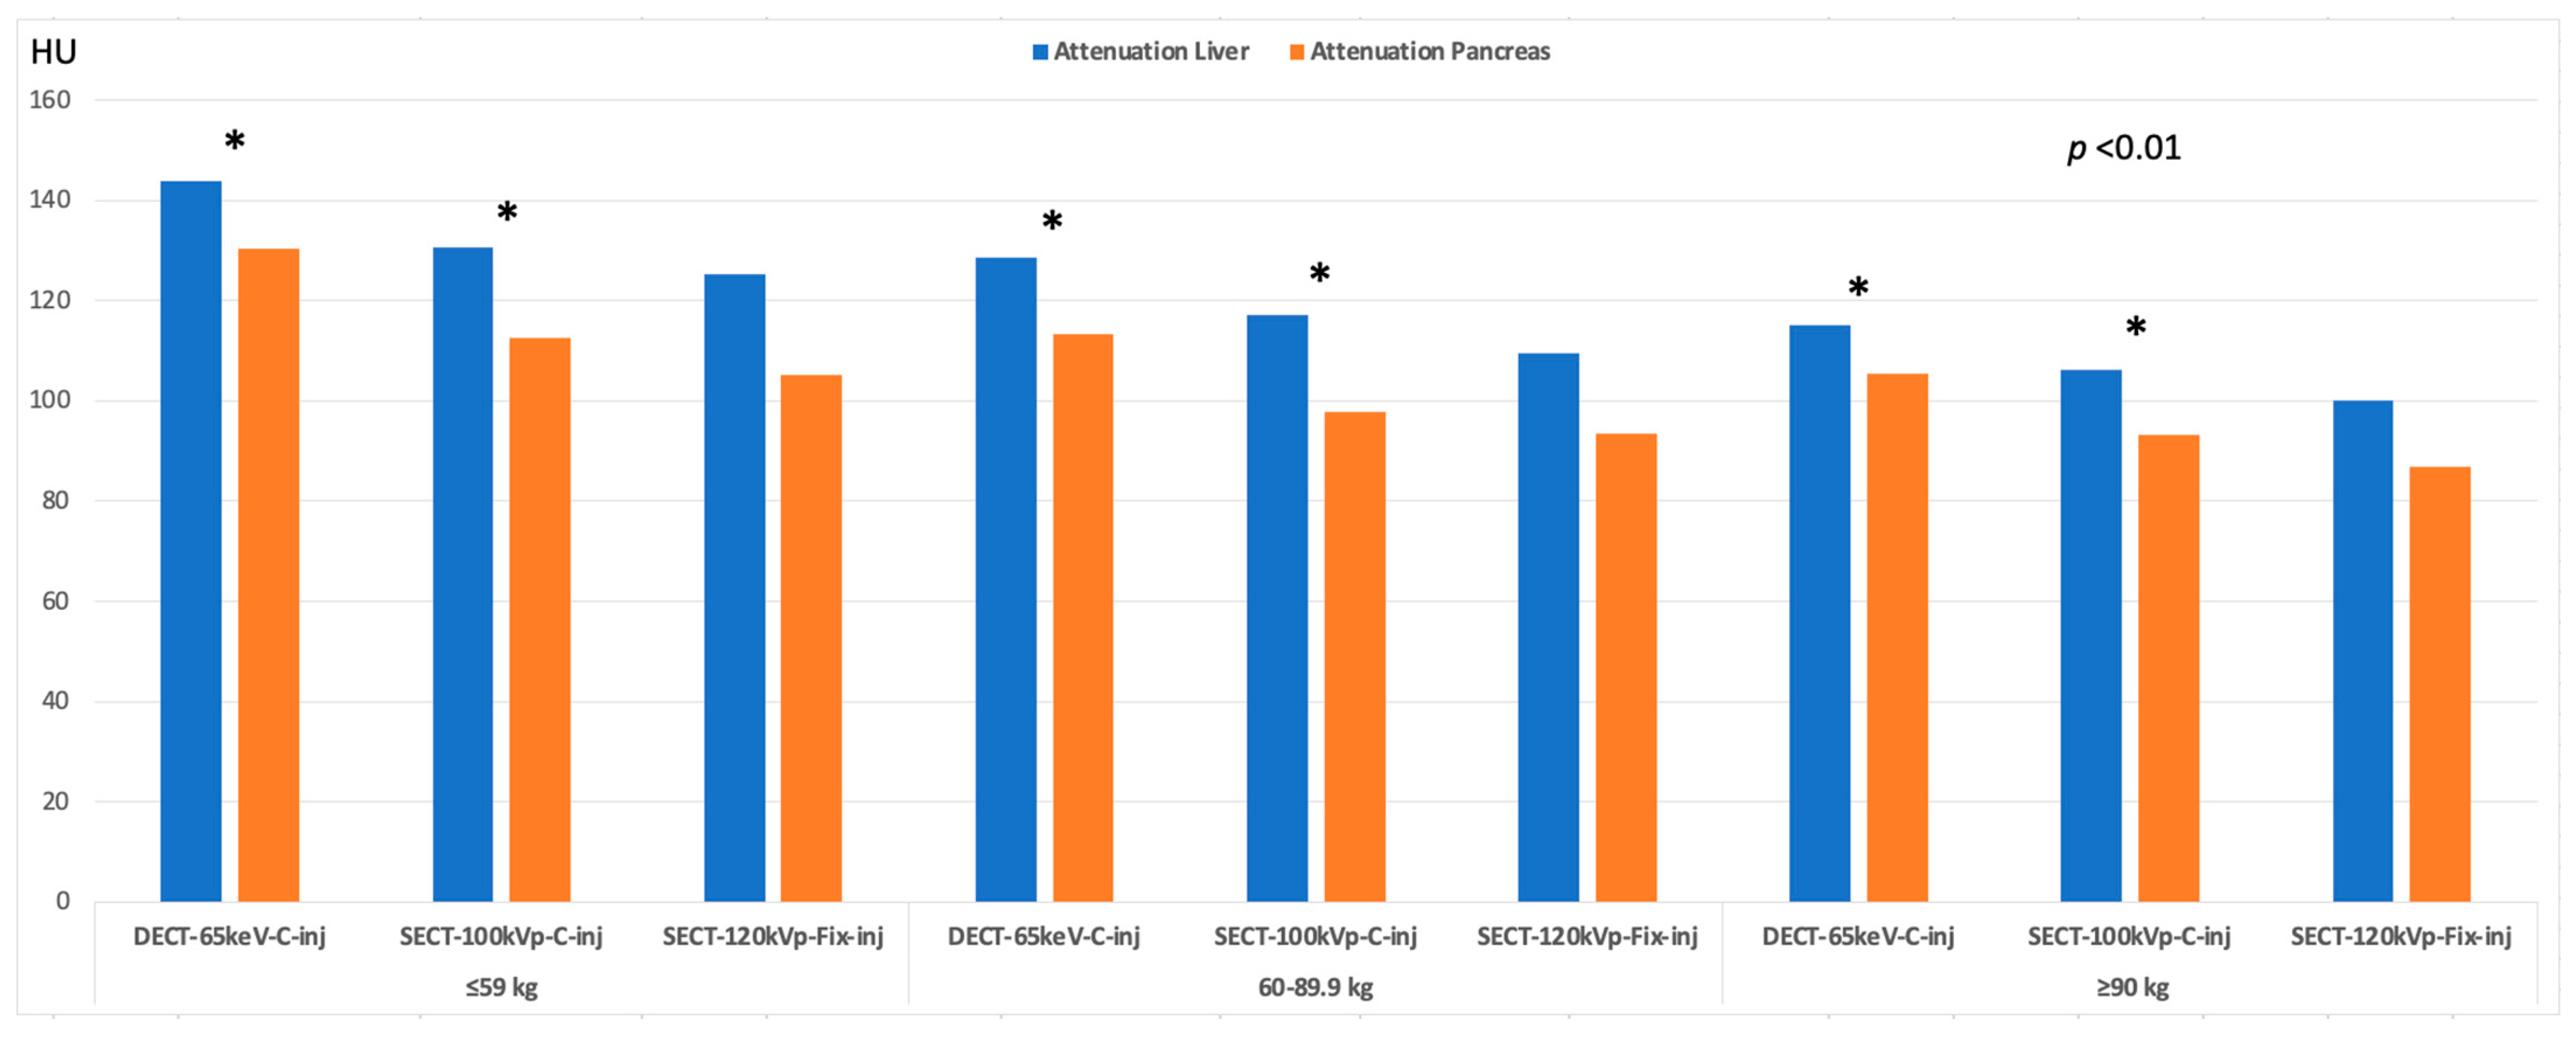

3.3. Image Quality

| ≤59.9 kg | 60–89 kg | ≥90 kg | Overall p-Value | p-Value ≤59.9 kg vs. 60–89 kg | p-Value ≤59.9 kg vs. 90 kg | p-Value 60–89 kg vs. ≥ 90 kg | |

| SECT-100kVp-C-inj | |||||||

| Attenuation | |||||||

| Liver | 130.60 | 117.13 | 106.24 | <0.001 | 0.032 | <0.001 | NS |

| ±13.89 | ±22.55 | ±20.53 | |||||

| Pancreas | 112.49 | 97.73 | 93.131 | <0.001 | 0.002 | <0.001 | NS |

| DECT(65-keV)-C-inj | |||||||

| Attenuation | |||||||

| Liver | 143.77 | 128.71 | 115.04 | <0.001 | <0.001 | <0.001 | 0.002 |

| ±17.24 | ±12.17 | ±15.76 | |||||

| Pancreas | 130.46 | 113.33 | 105.48 | <0.001 | <0.001 | <0.001 | NS |

| SECT-120kVp-Fix-inj | |||||||

| Attenuation | |||||||

| Liver | 115.27 | 101.51 | 93.41 | <0.001 | <0.001 | <0.001 | 0.012 |

| ±18.66 | ±19.04 | ±18.86 | |||||

| Pancreas | 105.25 | 93.53 | 86.75 | <0.001 | <0.001 | <0.001 | 0.040 |

| ±16.23 | ±15.23 | ±15.77 | |||||